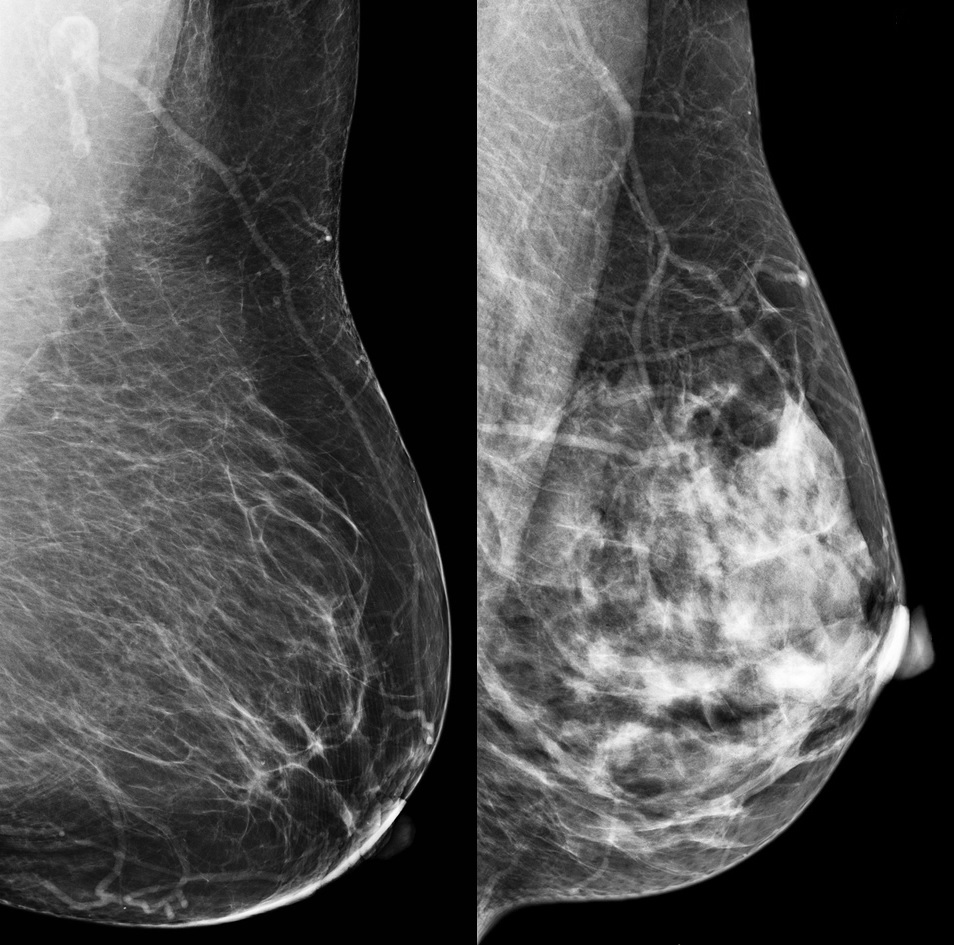

Breast density refers to the appearance of breast tissue in a mammogram. High breast density can mask signs of breast cancer in mammograms; dense breast tissue appears white, as does breast cancer. High breast density is also, in itself, a risk factor for breast cancer. Your breasts could lie anywhere along a spectrum from low to high density. The radiologists who examine your mammogram can tell how dense your breasts are, but this information is not currently routinely shared with women in New Zealand. Women with extremely dense breasts are at greater risk of breast cancer than those with low or average density. Ultrasound or MRI, in addition to mammograms, can improve detection of breast cancer in dense breasts. Breast imaging experts in Europe and the US now recommend that women be advised of their density and counselled to undertake extra screening.